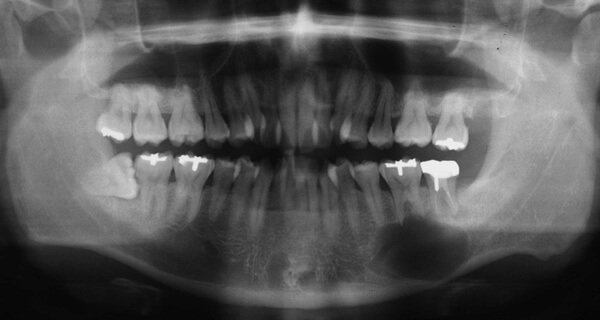

歯原性腫瘍